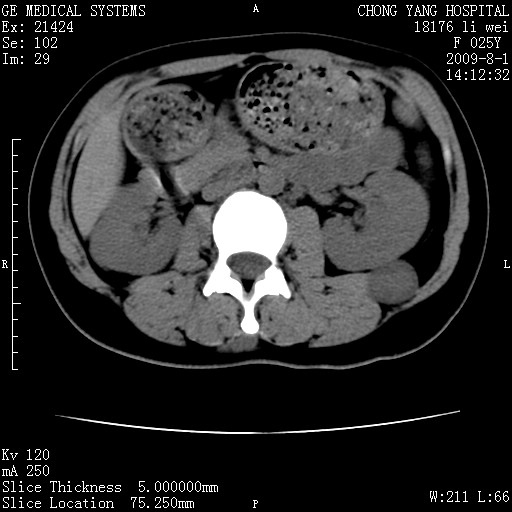

以下是引用pujunzhi在2009-8-1 20:23:00的发言:[br]胸椎旁及背部肌间良性病变,范围广,边界清,沿肌间生长,考虑淋巴管瘤、血管瘤,建议增强扫描。

以下是引用拾荒者在2009-12-30 21:45:00的发言:[br]ct21383:神经纤维瘤病( nf) [br] [br] 神经纤维瘤病。四肢都有,影响美观,四肢上的手术了。[br] [br] [br]谢谢!